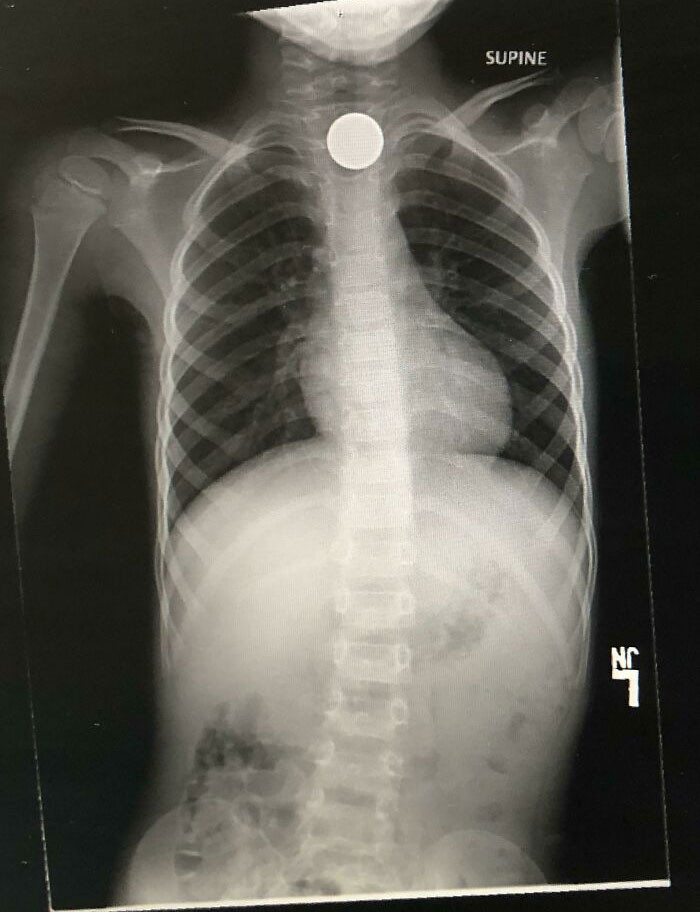

Kid swallows a nickel, and parents had to pay $4,400 to have it removed.

Kid swallows a nickel, and parents had to pay $4,400 to have it removed.Kingsdontbeg